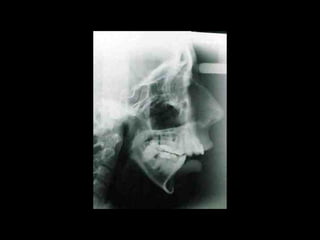

Valoración Clínica de la Paciente

En términos generales podemos decir que la

paciente tiene una cara armónica y aceptable,

sin embargo observaciones métricas delatan:

Laterognatia, manifestada por 3 grados de desviación del

Mentón con respecto a la línea media real.

Hipoplasia moderada del maxilar del lado derechoHipoplasia moderada del maxilar del lado derecho

Perfil cóncavoPerfil cóncavo

Ligera incompatibilidad labialLigera incompatibilidad labial

Depresión malarDepresión malar

La paciente muestra una franca disgnatia, clínicamente

observamos malposición dentaria secundaria a la falta de

armonía máxilomandibular.

Marcada Clase III

Hábito Lingual

Sobremordida horizontal: –1.5 mm

Sobremordida vertical: + 1 mm.